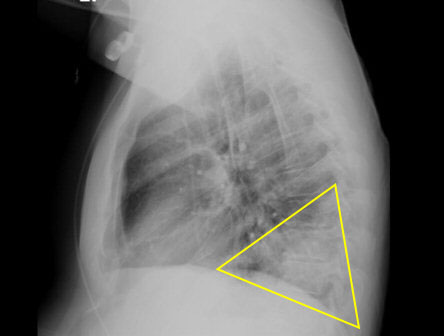

chest x-ray

Test

[Figure caption and citation for the preceding image starts]: Chest x-ray (lateral) showing infection: posterior segment of lower lobe consistent with pneumonia; the area in the triangle is normally clear (black). confirmed with positive urinary antigen testFrom the personal collection of Dr Forest W. Arnold; used with permission [Citation ends].

Result

Legionnaires' disease: lobar infiltrate; Pontiac fever: normal